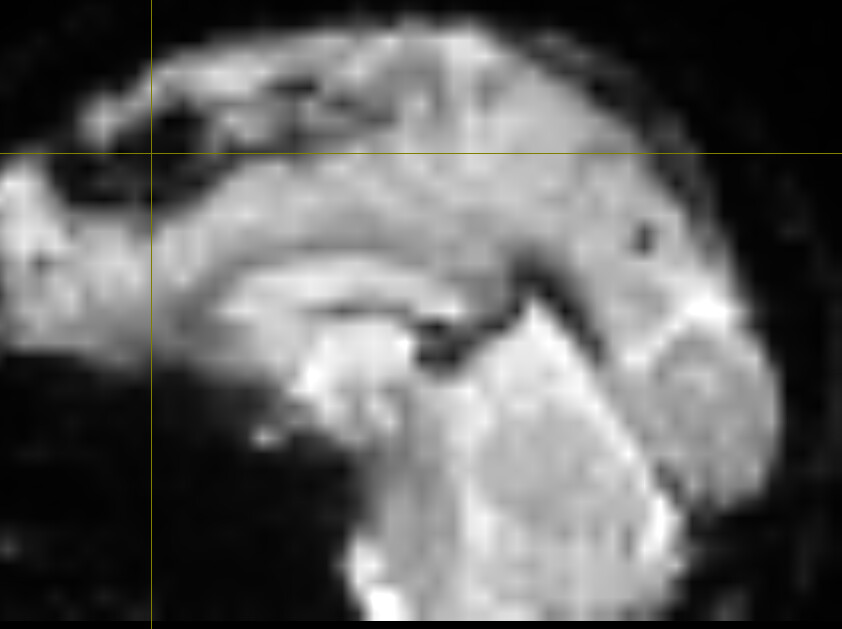

Upon further inspection, I noticed a midline “something” in the anatomical scan (below, anomaly marked by crosshair) extending several slices:

Which appears as a signal-void region, affecting LR_epi (one top) and RL_bold (two bottom) differently: